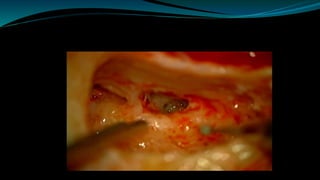

 Cochleostomy isperformed  Using 1 mm diamond bur ,small cochleostomy is made immediately anterior and inferior to the round window membrane  This allows direct access to the Scala tympani of cochlear basal turn.

• The electrodearray is inserted into the scala tympani of the cochlea • Undue force should not be used during electrode insertion to avoid electrode kinking within the cochlea and minimize insertional trauma to surviving neural elements within the cochlea.

The cochleostomy isthen plugged with small pieces of temporalis muscle or fascia.